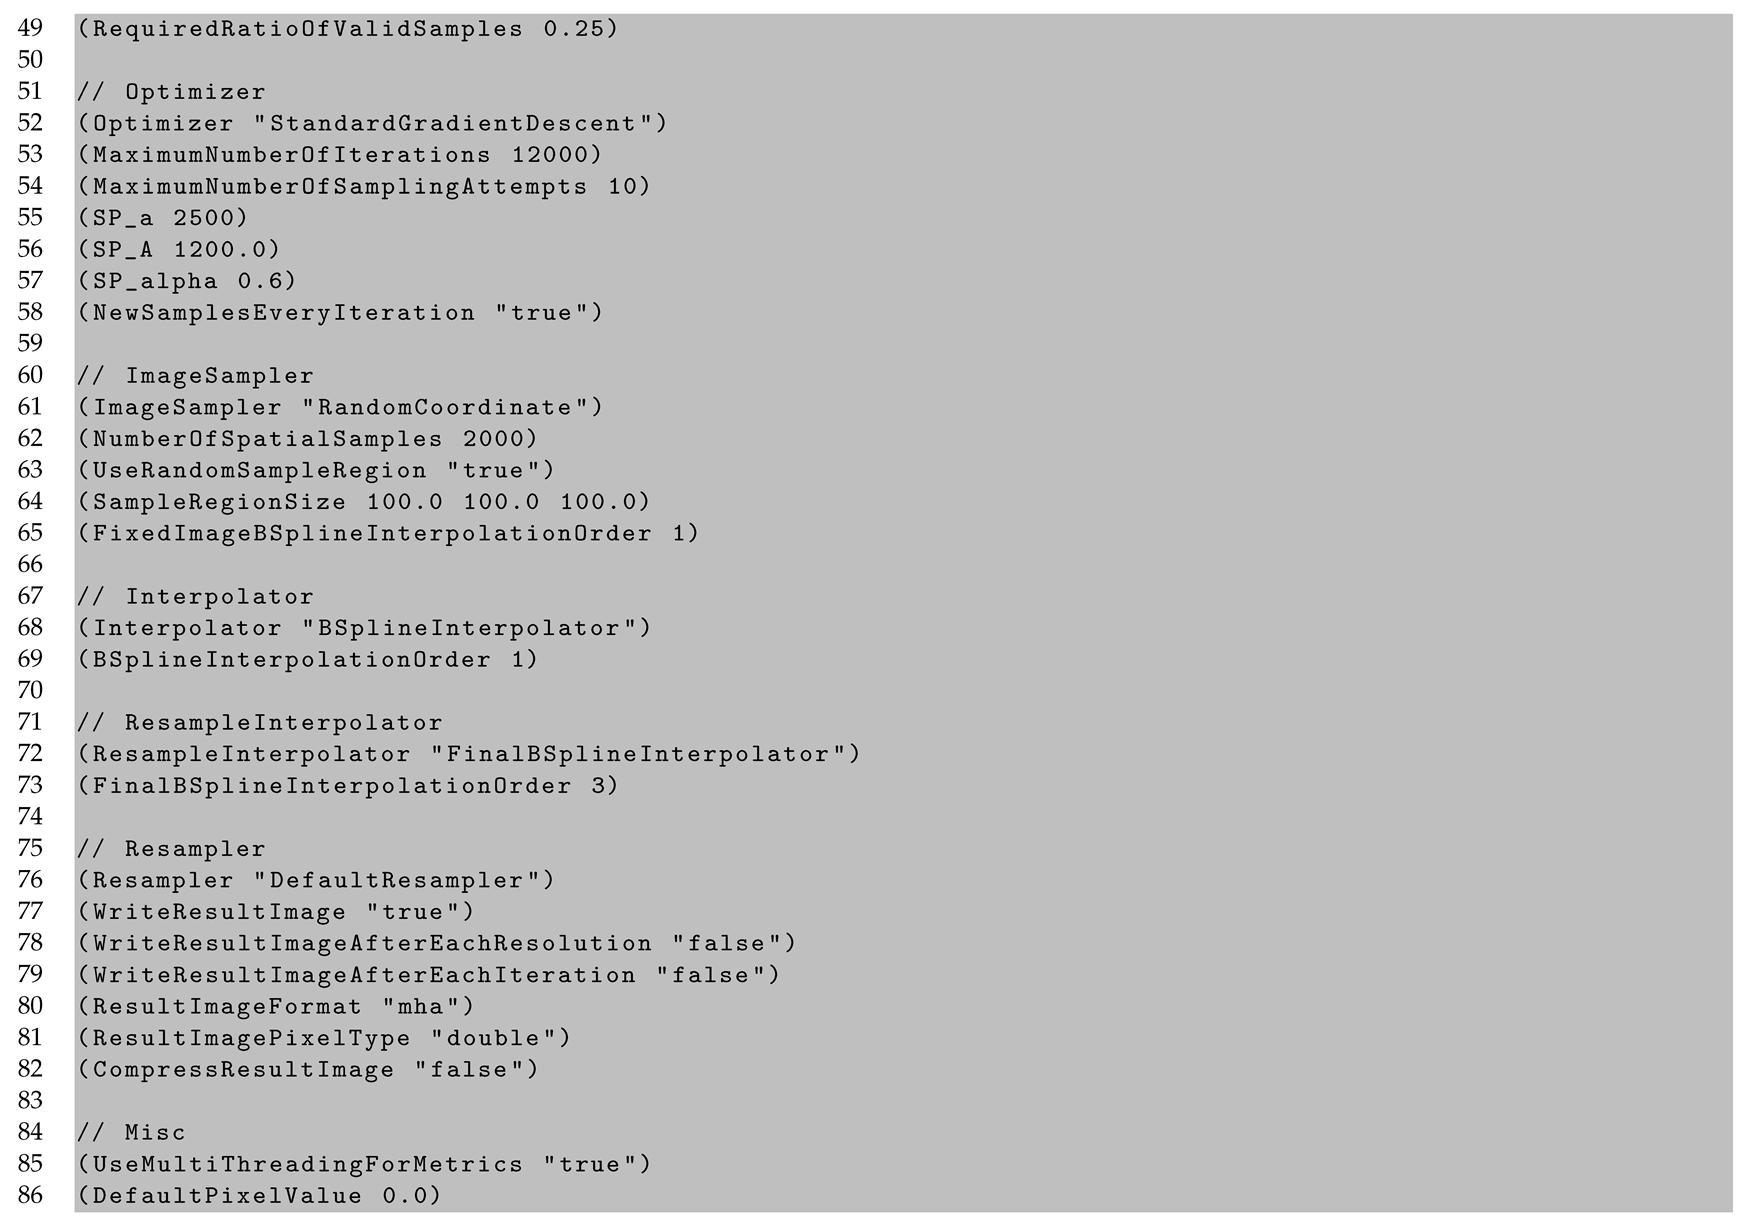

2.6. Cell Density Maps to Ex Vivo T1 Registration

Appendix C. In Vivo to Ex Vivo Registration